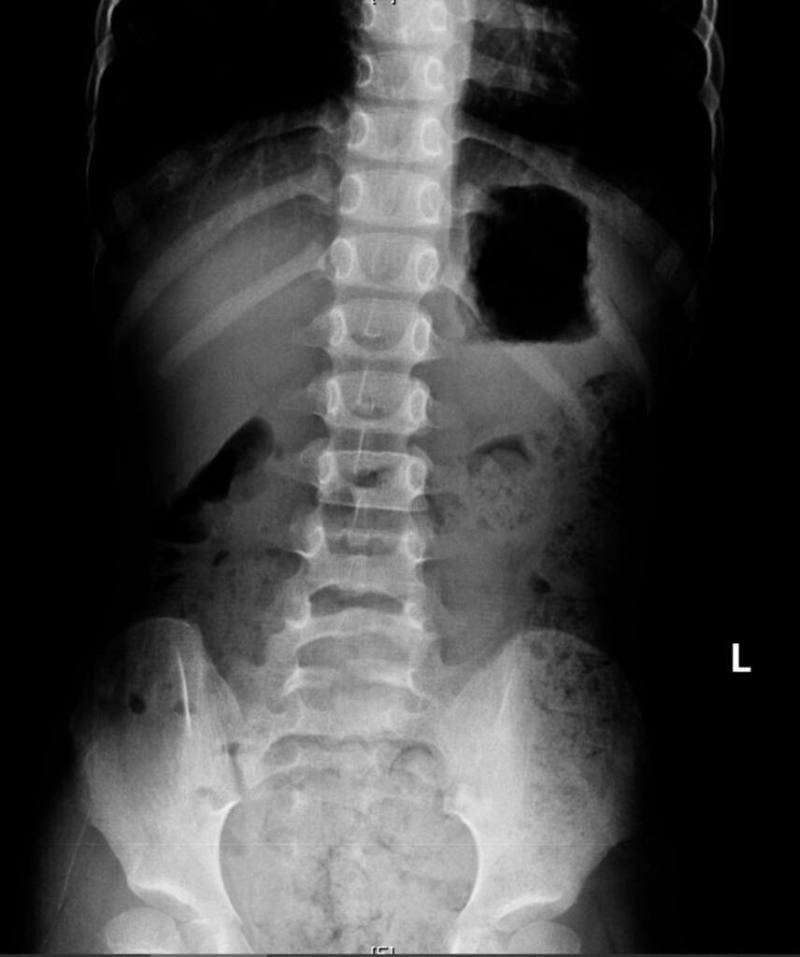

高雄一名男童近日因腹痛、冒冷汗被送到阮綜合醫院急診,X光檢查發現滿肚子都是大便;醫師提醒,長期便祕恐影響食慾與成長,家長應掌握餐後便意時機,協助孩子建立規律排便習慣。(阮綜合醫院提供)

(中央社訊)高雄一名11歲男童近日因腹痛、冒冷汗、嘴唇發紫、手腳冰冷被送到阮綜合醫院急診,X光檢查發現滿肚子都是大便;醫師提醒,家長要建立孩子規律排便習慣,可在飯後便意強時提醒上大號。

11歲男童近日因腹痛、嘴唇發紫送急診,經X光檢查診斷為便秘。灌腸後排出大量糞便,症狀立刻緩解。男童母親表示,孩子習慣邊上廁所邊玩手機,常被催促太久才匆忙結束,也不清楚是否排便乾淨。